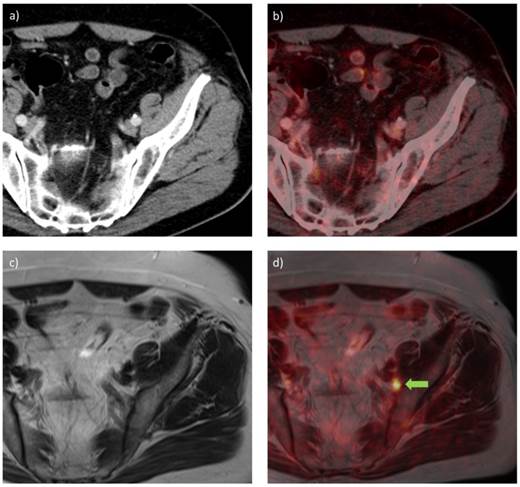

In a subsequent study, 68Ga-HBED-CC-PSMA PET/CT (150 MBq) was compared with 68Ga-HBED-CC-PSMA PET/MRI to evaluate whether PET/MRI could have additional value in the detection of PCa lesions [49]. Twenty patients (median PSA: 2.62 ng/ml, range: 0.51-73.60) were scanned with PET/CT 1 h p.i. and PET/MRI 3 h p.i.. Out of the 75 lesions which were characterized further, four lesions unclear in PET/CT could be established being PCa lesions in PET/MRI. Pathological lesions visible on PET often correlated with signals on MRI, offering a considerable advantage for PET/MR imaging. Overall, PCa was detected more easily and more accurately with 68Ga-HBED-CC-PSMA PET/MRI than with PET/CT. In figure 4, PET/CT and PET/MRI images of one patient are displayed, demonstrating that a suspect lymph node could be detected with 68Ga-HBED-CC-PSMA PET/MRI but did not show increased PSMA ligand uptake in PET/CT. A potential disadvantage of PET/MRI imaging was the appearance of halo artefacts around the bladder and kidneys, resulting in a reduced PET signal, and potentially making lesions in their vicinity undetectable (figure 5) [49].

Figure 4

68Ga-HBED-CC-PSMA PET/CT (a, b) and PET/MRI (c, d) images of a patient with PCa with recurrent disease in an inguinal lymph node (PSA 0.9 ng/ml) after radical prostatectomy, scanned at 1 h and 3 h p.i., using PET/CT and PET/MRI, respectively. a) CT image, b) PET/CT fusion image, c) MR image (T2-weighted with contrast medium and turbo spin echo), d) PET/MRI fusion image. A metastatic lymph node is visible in the PET/MRI fusion image (green arrow), while the same lesion could not be visualized with PET/CT.

Theranostics Image